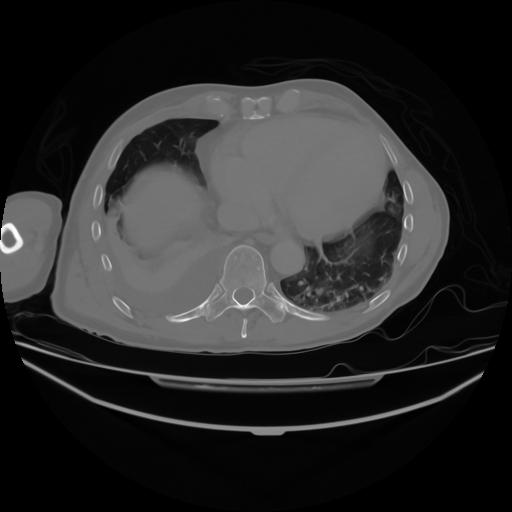

4 CUERPO,CE,Axial,3.0,CUERPO,,